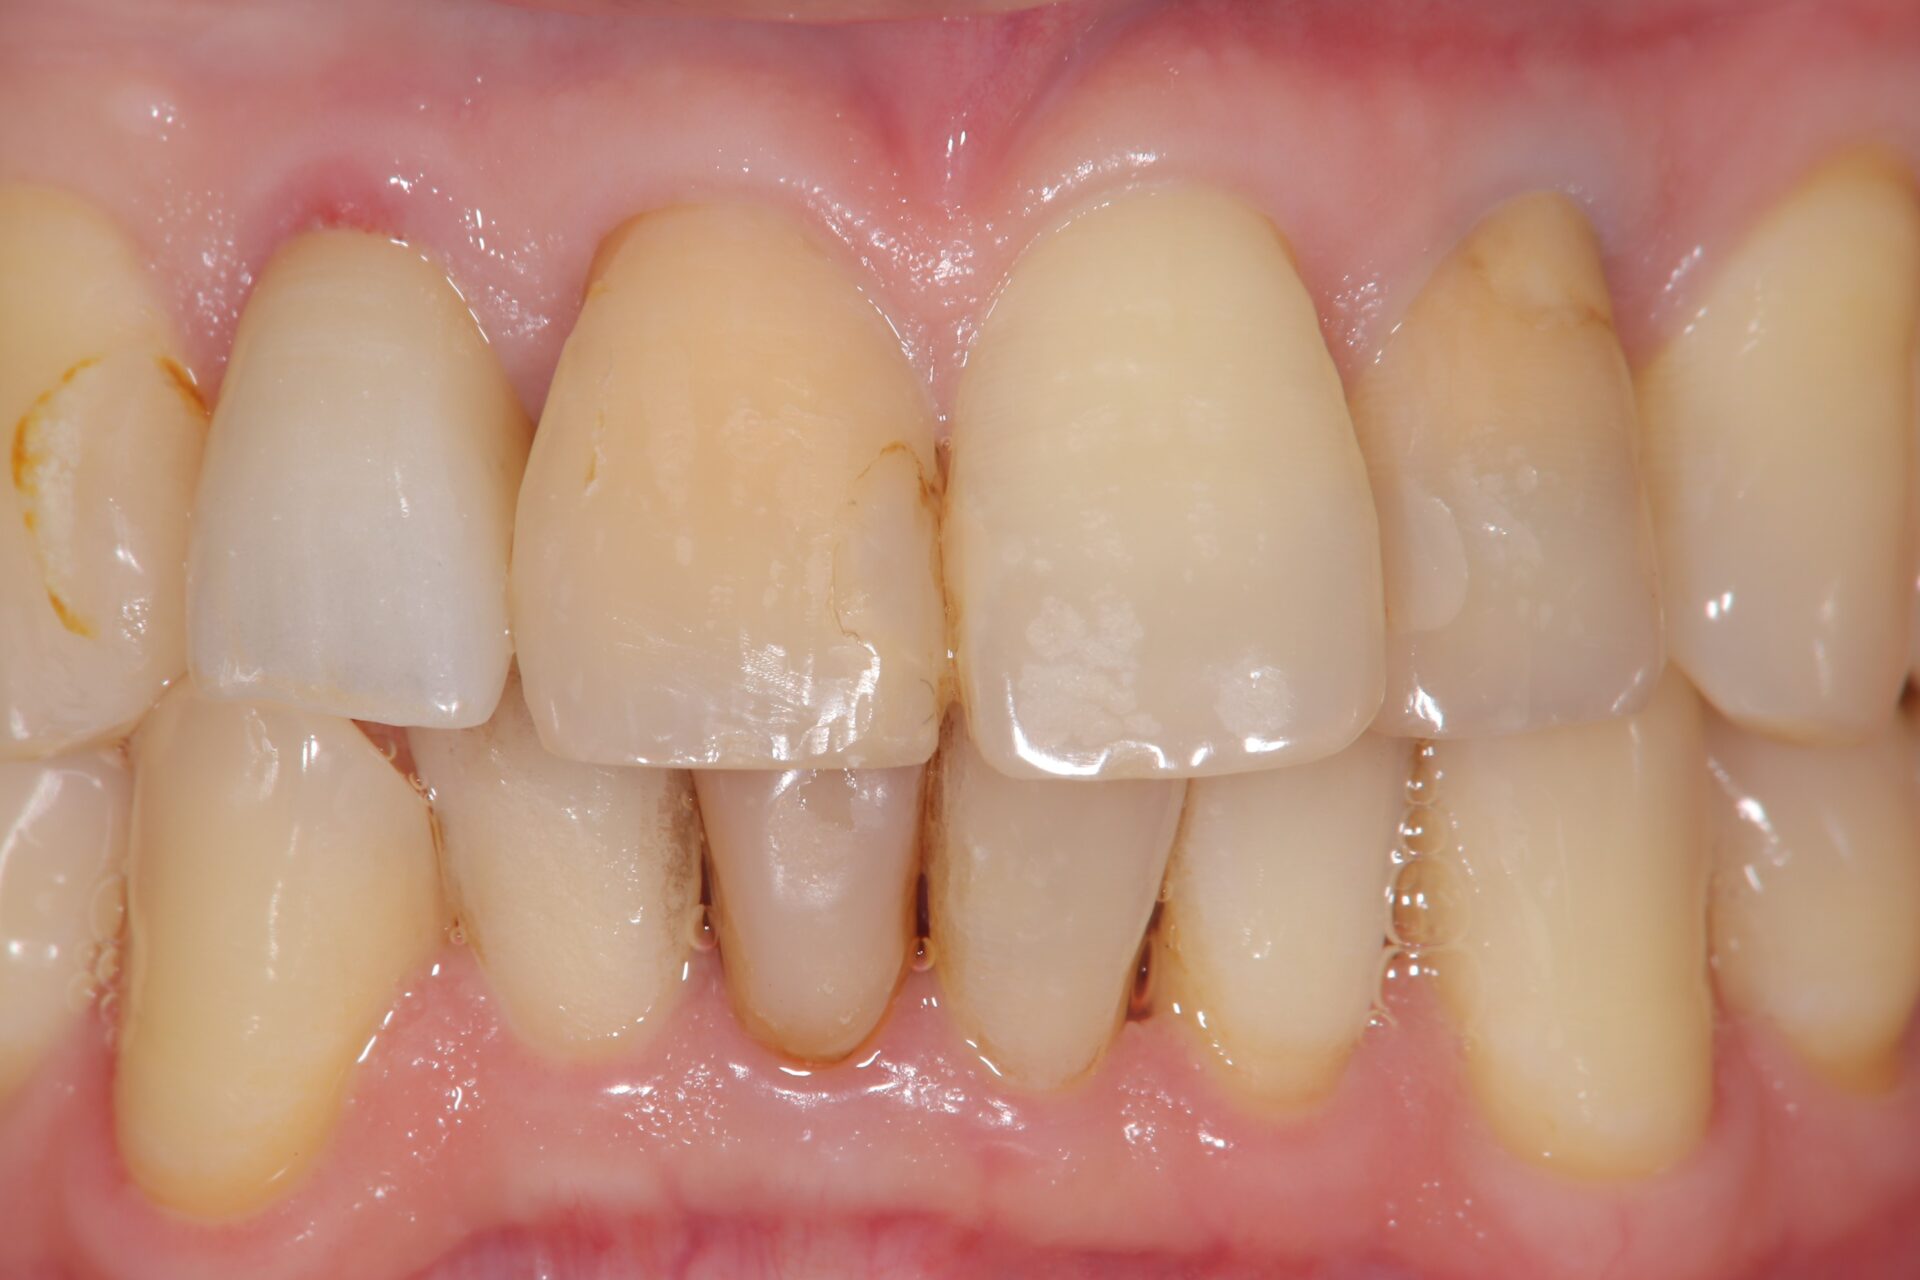

2023.1/25 他院で被せ物を作成した歯が腫れて痛みがあるということでご来院。

2024.6/5 被せ物は外し、当院で改めて根っこの治療を行いました。

2024.9/5 右上2番の治療が終わり、ジルコニアクラウンの被せ物を作成しました。

治療部位 | 右上2番 |

費用 | 保険分+自費で約11万円 |

治療期間 | 21ヶ月 |

注意事項(リスク・副作用など) | 治療の刺激や薬剤の刺激により、治療後数時間から数日後に痛みや腫れが生じる場合があります。 |

カテゴリ | 歯内療法 |